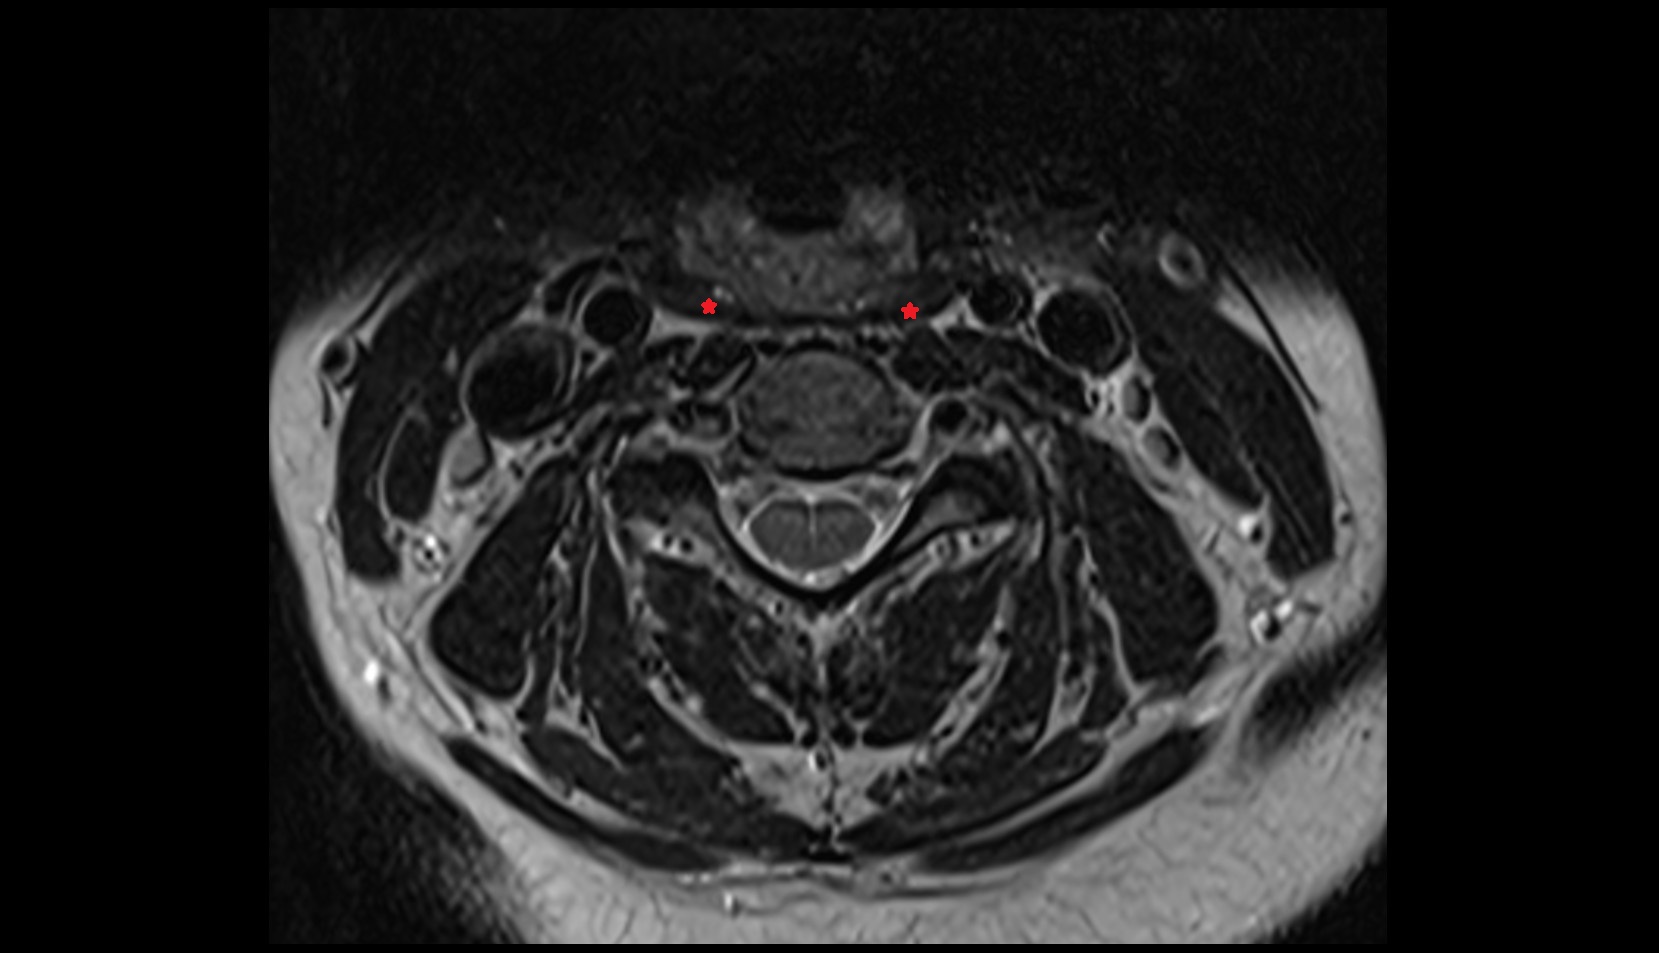

- Facet joint of vertebra (Zygapophyseal joints)